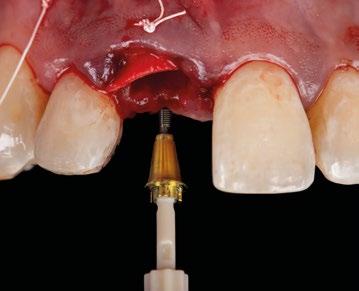

10.- Colocamos implante Nobel Biocare N1TM TiUltra de 3,5x13. (Figura 26)

11.- Observamos el torque obtenido de 50N por lo tanto podemos realizar carga inmediata. (Figura 27)

12.- Colocamos aditamento N1TM Base XealTM con el fin de trabajar la prótesis a nivel gingivall. (Figura 28)